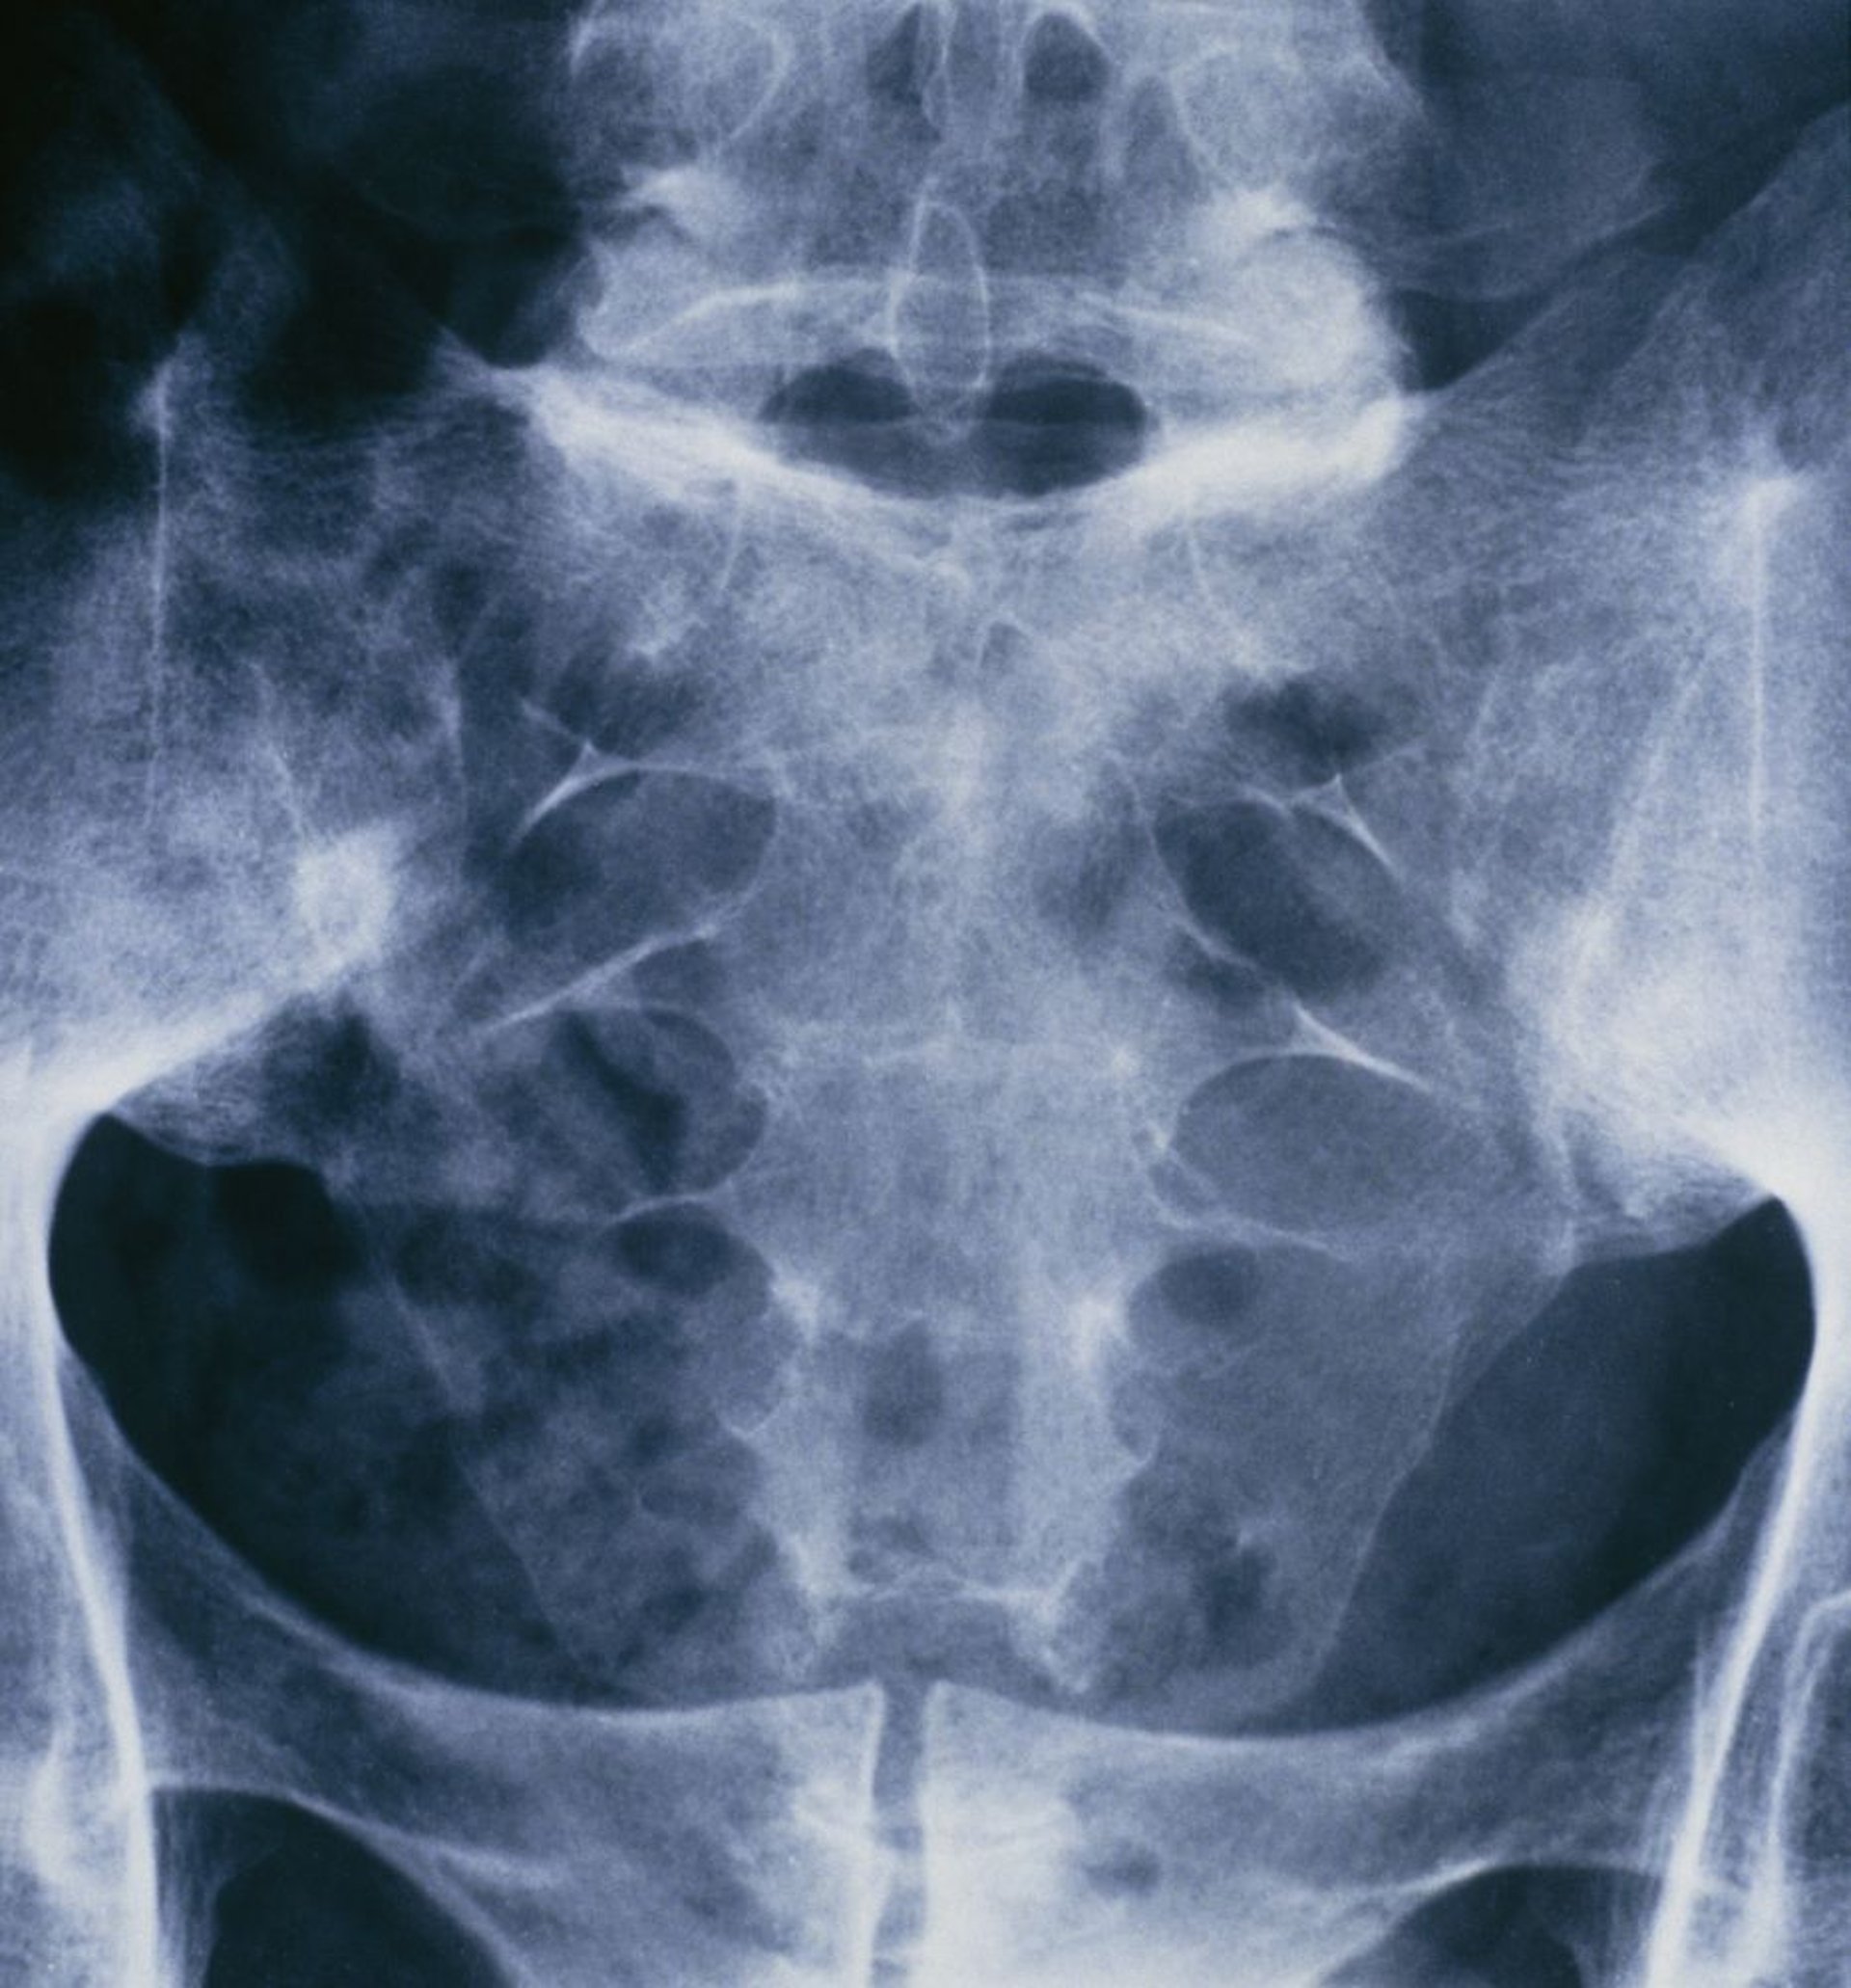

Spondylarthrite ankylosante (sacroiléite)

Cette radiographie du bassin et du rachis sacré d'une personne souffrant de spondylarthrite ankylosante montre la fusion des deux articulations sacro-iliaques.

ST. BARTHOLOMEW'S HOSPITAL, LONDON/SCIENCE PHOTO LIBRARY